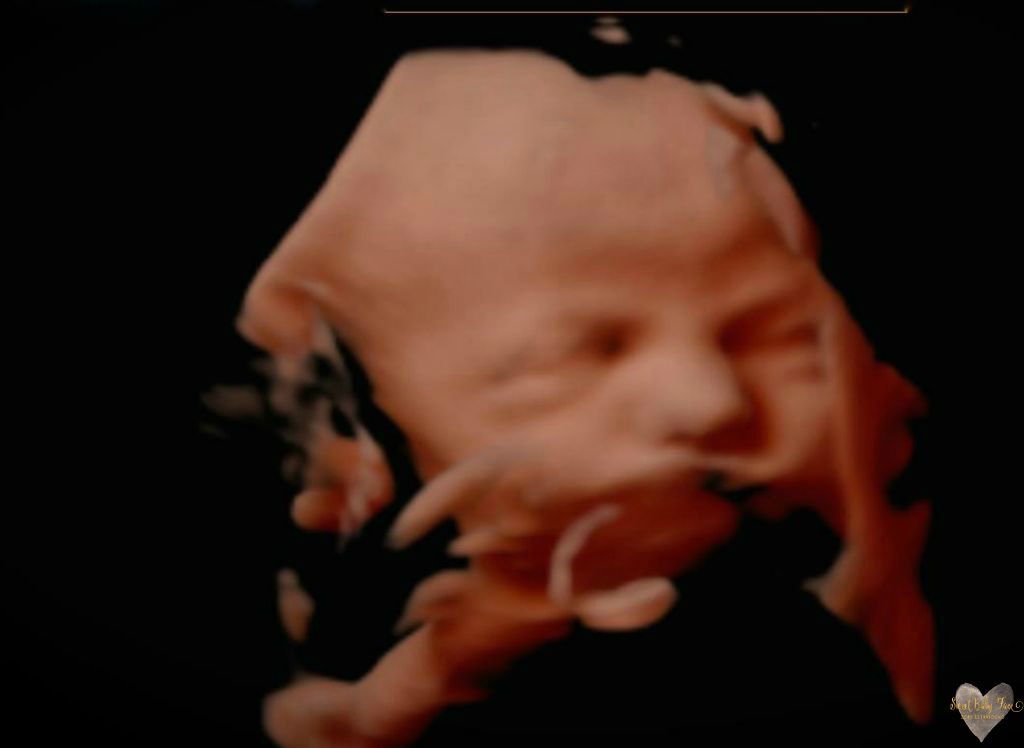

3D/4D/5D Ultrasound Gallery

Take a peek at our Photo Gallery. All of our 2D, 3D, 4D, HD elective ultrasound images are truly ours. They come directly off our machine from our highly trained staff. We can start getting great 3D/4D images as early as 10 weeks!